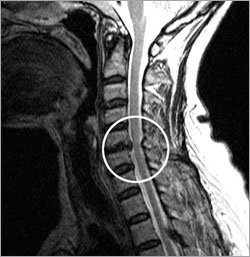

頸椎間盤突出症是頸椎之間的椎間盤突出壓迫周圍神經的病症。如果後頸的疼痛或麻的感覺沿著神經影響到肩部和手臂,就應該考慮是否患上了頸椎間盤突出症。

最重要的判定標準是看是否壓迫了中樞神經。如果突出的椎間盤嚴重壓迫中樞神經,則使人難以入睡等非常痛苦。在這種情況下,即使是輕輕摔倒,也有可能導致全身癱瘓,所以需要進行手術治療。

雖然椎間盤壓迫了中樞神經,但是也有疼痛或麻的感覺較輕的情況。根據醫生的判斷,一般有兩個治療方案,一是必須立即手術治療,二是接受物理治療的同時進一步觀察。應該充分地研究壓迫神經的程度和症狀以及手術的安全性,然後再決定是否進行手術。

椎間盤只壓迫末梢神經的情況,大部分採取藥物治療和物理治療雙管齊下的方法。但即使是只壓迫了末梢神經,但如果壓迫程度嚴重,手和胳膊的感覺遲鈍,而且變得無力,也應考慮接受手術治療。